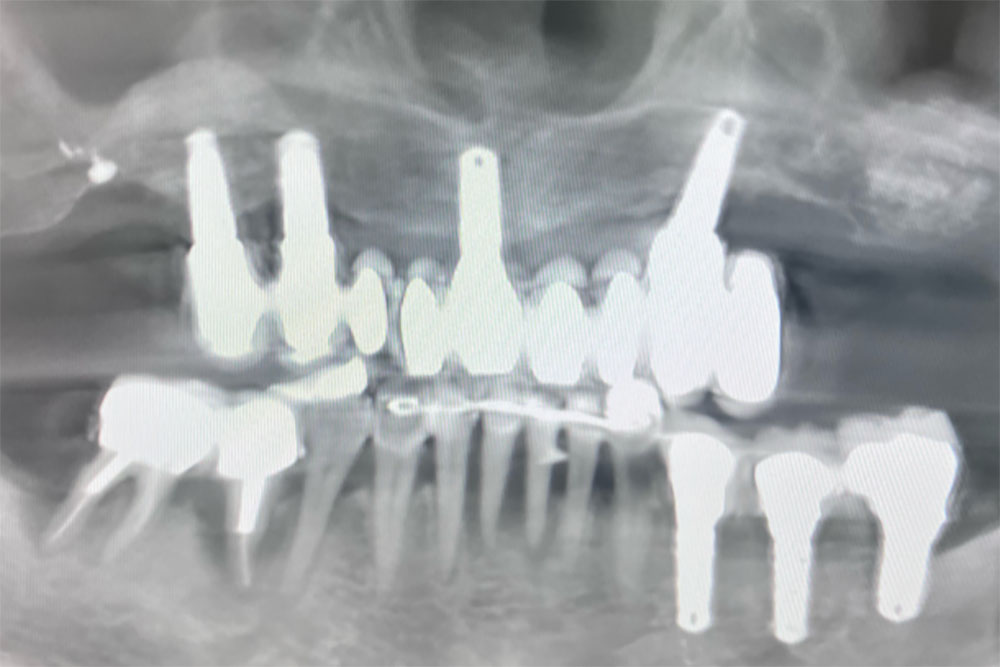

Oui. Lors de ce cas traité à Saint-Fons, certains implants issus d’un traitement antérieur étaient parfaitement ostéo-intégrés. Plutôt que de tout déposer, une analyse radiologique (CBCT) et clinique approfondie a permis de conserver les implants fiables et d’intégrer ces ancrages dans une nouvelle stratégie prothétique optimisée.

Notre approche repose sur une planification numérique complète (CBCT, workflow digital), une analyse biomécanique précise et une stratégie conservatrice intelligente : préserver ce qui fonctionne, reconstruire ce qui est défaillant. Nous intervenons sur des cas d’implantologie complexe, réhabilitations complètes maxillaires et reprises d’échecs implantaires.